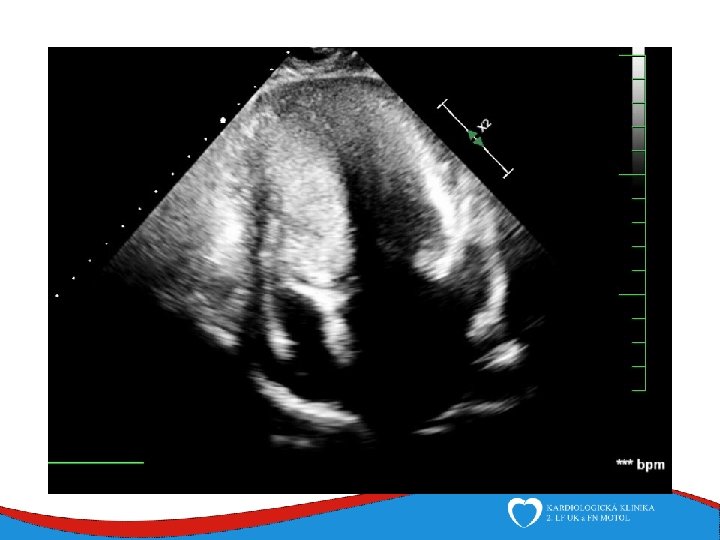

Diagnosis Family history Phisical examination ECG systolic murmur at the apex and lower left sternal border heterogenous LVH, patol. Q , QS, …. ECHO – golden standard MRI septal thickness more than 15 mm, papillary muscles hypertrophy, mitral anterior leaflet elongation, pressure gradient regions of myocarrdial fibrosis regions of late gadolinium enhancement (LGE) Stress test blood pressure responce ECG monitoring ventricular arrhythmia Selective coronarography

ECHO – anterior wall akinesis, LV EF 35%, mild mitral regurgitation, no dilation of right-sided chambers, no pericardial effusion

Tako-tsubo